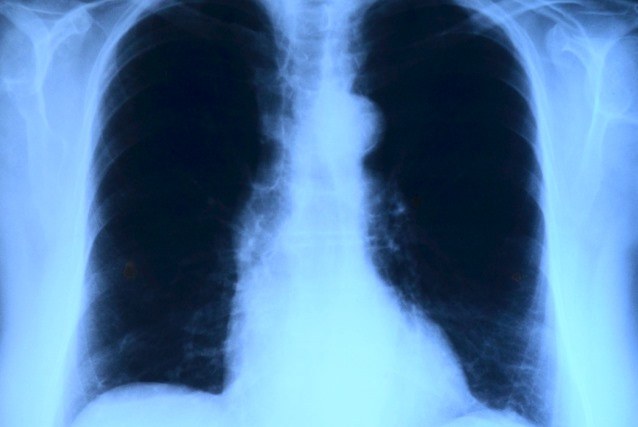

L’ipertensione polmonare è una patologia che implica un aumento della pressione del sangue all'interno dei vasi arteriosi del polmone dovuta all'ispessimento delle pareti dei vasi, al restringimento, al danneggiamento o all’ostruzione dei vasi stessi. Questa condizione sottopone il ventricolo cardiaco destro (che pompa il sangue verso i polmoni) a un sovraccarico di pressione e volume, che può condurlo all’insufficienza funzionale e allo scompenso.

Se non opportunamente trattata, l'ipertensione polmonare può degenerare, causando ulteriore restringimento dei vasi sanguigni e aggravando i sintomi tipici della patologia: respirazione difficoltosa, soprattutto durante sforzi fisici, stanchezza o affaticabilità, svenimenti e, nelle fasi avanzate della patologia, respirazione difficoltosa anche a riposo, dolori al petto segno di sofferenza cardiaca ed edema agli arti inferiori.